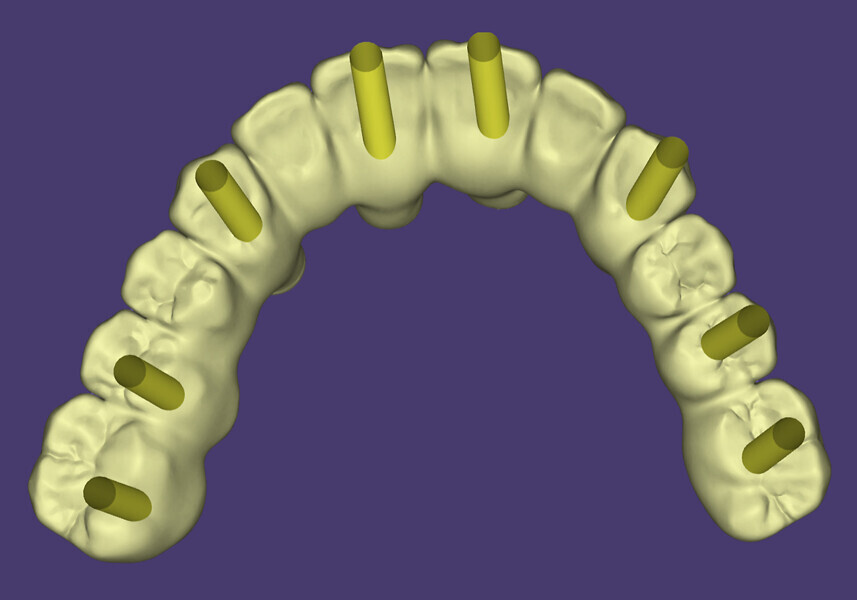

The collected data, along with preliminary plans for potential implant receptor sites (Blue Sky Plan, Blue Sky Bio), was submitted to the laboratory (ROE Dental Laboratory) for review. The 3D data from the CBCT scan was then merged with the IOS data set to aid in determining a restoratively driven solution for both arches. The laboratory then designed provisional full-arch screw-retained restorations utilising CAD software at the designated VDO required for the prostheses. The desired tooth position as visualised with the 3D reconstructed volume of bone helped to determine the most favourable implant receptor sites. A virtual remote planning session was held with the laboratory to finalise the full-template guided surgical plan (CHROME GuidedSMILE, ROE Dental Laboratory), which incorporated a 2 mm increase in the VDO, and the case was sent for production. The CHROME GuidedSMILE protocol consists of several component parts, which provide a stackable solution with metallic scaffolding to control the bone reduction, the preparation of the osteotomies, full-template guidance of the implants into the bone, control of implant depth, trajectory and rotational indexing, the positioning of the MUAs and the delivery of the provisional restorations.1

Fig. 11b: Maxillary intra-oral scan.

Fig. 11c: Mandibular intra-oral scan.